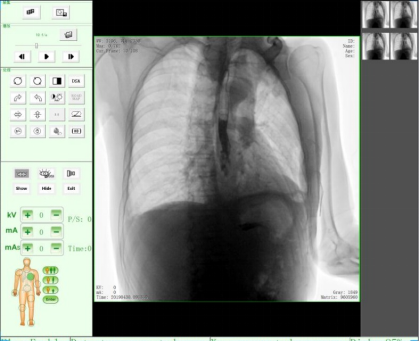

隨著人們健康意識不斷提高,越來越多人重視健康體檢,而數字化DR拍片幾乎是體檢必檢項目之一,胸片結果正常DR報告顯示為:胸廓對稱,兩側肋骨、肋間隙正常;兩肺紋理清晰,未見明顯實質性浸潤;兩側肺門和縱隔影來見明顯異常;心臟大小、形態在正常范圍內;膈肌平滑,雙側肋膈角銳利時,則說明您一切正常。那么,數字化DR胸片報告不正常的結果有哪些呢?

2、密度不太高的、較為均勻的云絮片狀影,邊緣模糊,與正常肺間無清楚界限。

這就是在肺里該黑的地方變白了,它是由于急性炎癥的滲出所致,當肺部急性炎癥進展到某一階段時,肺泡內氣體即被由血管滲出的液體、蛋白及細胞所代替,形成滲出性實變。而這種實變取代了原先肺泡內的氣體,從而擋住了X線,致使在數字化DR片上呈現出一片白色陰影。

3、兩肺紋理增粗、紊亂,呈網狀或條索狀、斑點狀陰影。

老慢支,肺氣腫,肺心病,這時您的數字化DR片可能會呈現這種胸片,當進一步發展時,將會出現兩肺透亮度增加。由于肺泡過度通氣致使X光胸片上黑化度增加,即越黑透亮度越大。哮喘發作時同樣可見兩肺透亮度增加,呈過度充氣狀態。當然,X線攝影條件過高或是顯影時間過長也會導致這樣。

如果臨床表現為在原有咳嗽、咳痰的基礎上有逐漸加重的呼吸困難,甚至有胸悶、氣急、桶狀胸。常見的嚴重肺氣腫、肺大泡還會導致氣胸,也就是胸腔內的氣體將肺壓縮,使被壓縮的肺與胸壁間出現透明的含氣區,其中不見肺紋理。這些多是由白變黑的異常。